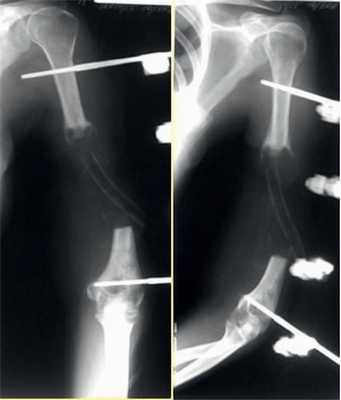

2. Больная В., 47 лет, поступила через 2 года после автотравмы с диагнозом: атрофический ложный сустав правой плечевой кости, перелом фиксатора (рис. 2). Рисунок 2. Рентгенограммы больной В., 47 лет (I), и функция конечности через 2 нед после операции (II). I: а - многооскольчатый перелом правой плечевой кости, б - интрамедуллярный остеосинтез, в - несостоятельность фиксатора через 3 мес, г - реостеосинтез пластиной с угловой стабильностью, д - перелом накостного фиксатора спустя 18 мес, е - реконструкция плечевой кости - накостный остеосинтез метафизарной пластиной с применением ротированного на сосудистой ножке надкостнично-кортикального аутотрансплантата, ж - консолидация ложного сустава через 5 мес; II - функция конечности через 2 нед после операции.

Больная П., 25 лет, поступила в стационар с жалобами на боли в левом локтевом суставе через 2 ч после травмы в результате падения на улице. При осмотре отмечены отек левого локтевого сустава, болезненность при пальпации, невозможность движений в суставе из-за боли. После клинико-рентгенологического обследования установлен диагноз: закрытый внутрисуставной оскольчатый чрезмежмыщелковый перелом левой плечевой кости со смещением отломков тип 13-С2 (рис. 2). Рисунок 2. Рентгенограммы больной П. с внутрисуставным оскольчатым чрезмежмыщелковым переломом левой плечевой кости со смещением отломков тип 13-С2.

На следующий день под новокаиновым блоком плечевого сплетения произведена операция: закрытая репозиция и чрескостный остеосинтез левой плечевой кости спице-стержневым аппаратом внешней фиксации конструкции А.И. Городниченко. Через разрезы кожи и мягких тканей по наружной поверхности левого плеча длиной до 5 мм введено 2 кортикальных стержня в диафиз плечевой кости, один кортикальный и один спонгиозный стержень и 2 спицы с упорной площадкой в мыщелки и надмыщелки плечевой кости. После фиксации проксимальных стержней в аппарате под контролем электронно-оптического преобразователя произведена закрытая репозиция с помощью съемных рукояток с последующей стабилизацией дистальных стержней и спиц (рис. 3). Рисунок 3. Рентгенограммы больной П. после остеосинтеза левой плечевой кости спице-стержневым аппаратом. Кожа вокруг стержней ушита одиночными швами. Кровопотеря в ходе операции 20 мл. Продолжительность операции 40 мин.

Послеоперационное течение без осложнений, проводили регулярные перевязки с обработкой кожи вокруг стержней и спиц растворами антисептиков и сменой асептических повязок. Швы вокруг стержней сняты через 8 дней после операции, пациентка выписана на амбулаторное лечение с рекомендациями по дальнейшему восстановительному лечению. Движения в левом локтевом суставе перед выпиской из стационара показаны на рис. 4. Рисунок 4. Рентгенограммы больной П. после остеосинтеза левой плечевой кости спице-стержневым аппаратом.

После консолидации перелома через 71 день произведен демонтаж аппарата (рис. 5). Рисунок 5. Рентгенограммы больной П. после остеосинтеза левой плечевой кости спице-стержневым аппаратом. Движения в левом локтевом суставе после демонтажа аппарата от 0 до 128° (рис. 6). Рисунок 6. Внешний вид больной П. после демонтажа аппарата (объем движений в левом локтевом суставе от 0 до 128°).